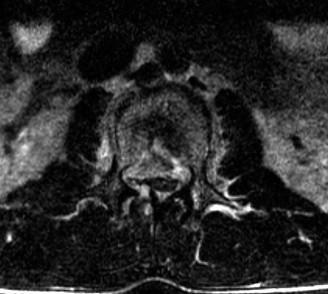

Initial trauma radiographs demonstrated a loss of anterior and middle column height at L1, with a focal kyphotic deformity. However, plain films are vastly insufficient for definitive surgical planning in thoracolumbar trauma. A high-resolution, fine-cut Computed Tomography (CT) scan of the entire spine was obtained. The CT images confirmed an L1 burst fracture with severe comminution of the vertebral body. Sagittal and axial reconstructions revealed 50% canal compromise secondary to a large retropulsed bone fragment originating from the posterosuperior aspect of the L1 vertebral body. Furthermore, the CT demonstrated 25 degrees of segmental kyphosis measured from the superior endplate of T12 to the inferior endplate of L1.

A critical finding on the axial CT slices was a vertical, split fracture propagating through the L1 lamina. This is a highly significant morphological feature. A lamina fracture in the setting of a burst fracture with retropulsion strongly correlates with a dural tear and potential entrapment of the cauda equina nerve roots. When the vertebral body bursts posteriorly, the pedicles are driven outward, and the lamina fractures as the spinal canal attempts to expand to accommodate the retropulsed bone. If the dura is lacerated, nerve roots can herniate through the dural defect and become incarcerated in the laminar fracture site.

Before rod placement, we must address the neural canal. Because of the lamina fracture and the 50% canal compromise, a direct posterior decompression (laminectomy) of L1 is performed. We carefully remove the fractured lamina. As suspected, a small dural tear is identified where the fractured bone edge lacerated the thecal sac. This is repaired primarily with 4-0 Nurolon and augmented with a dural sealant. By performing the laminectomy, we decompress the canal and remove the risk of nerve root entrapment during our subsequent reduction maneuvers.